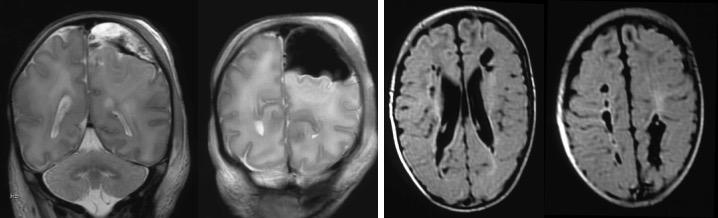

- l’HSD obstétrical